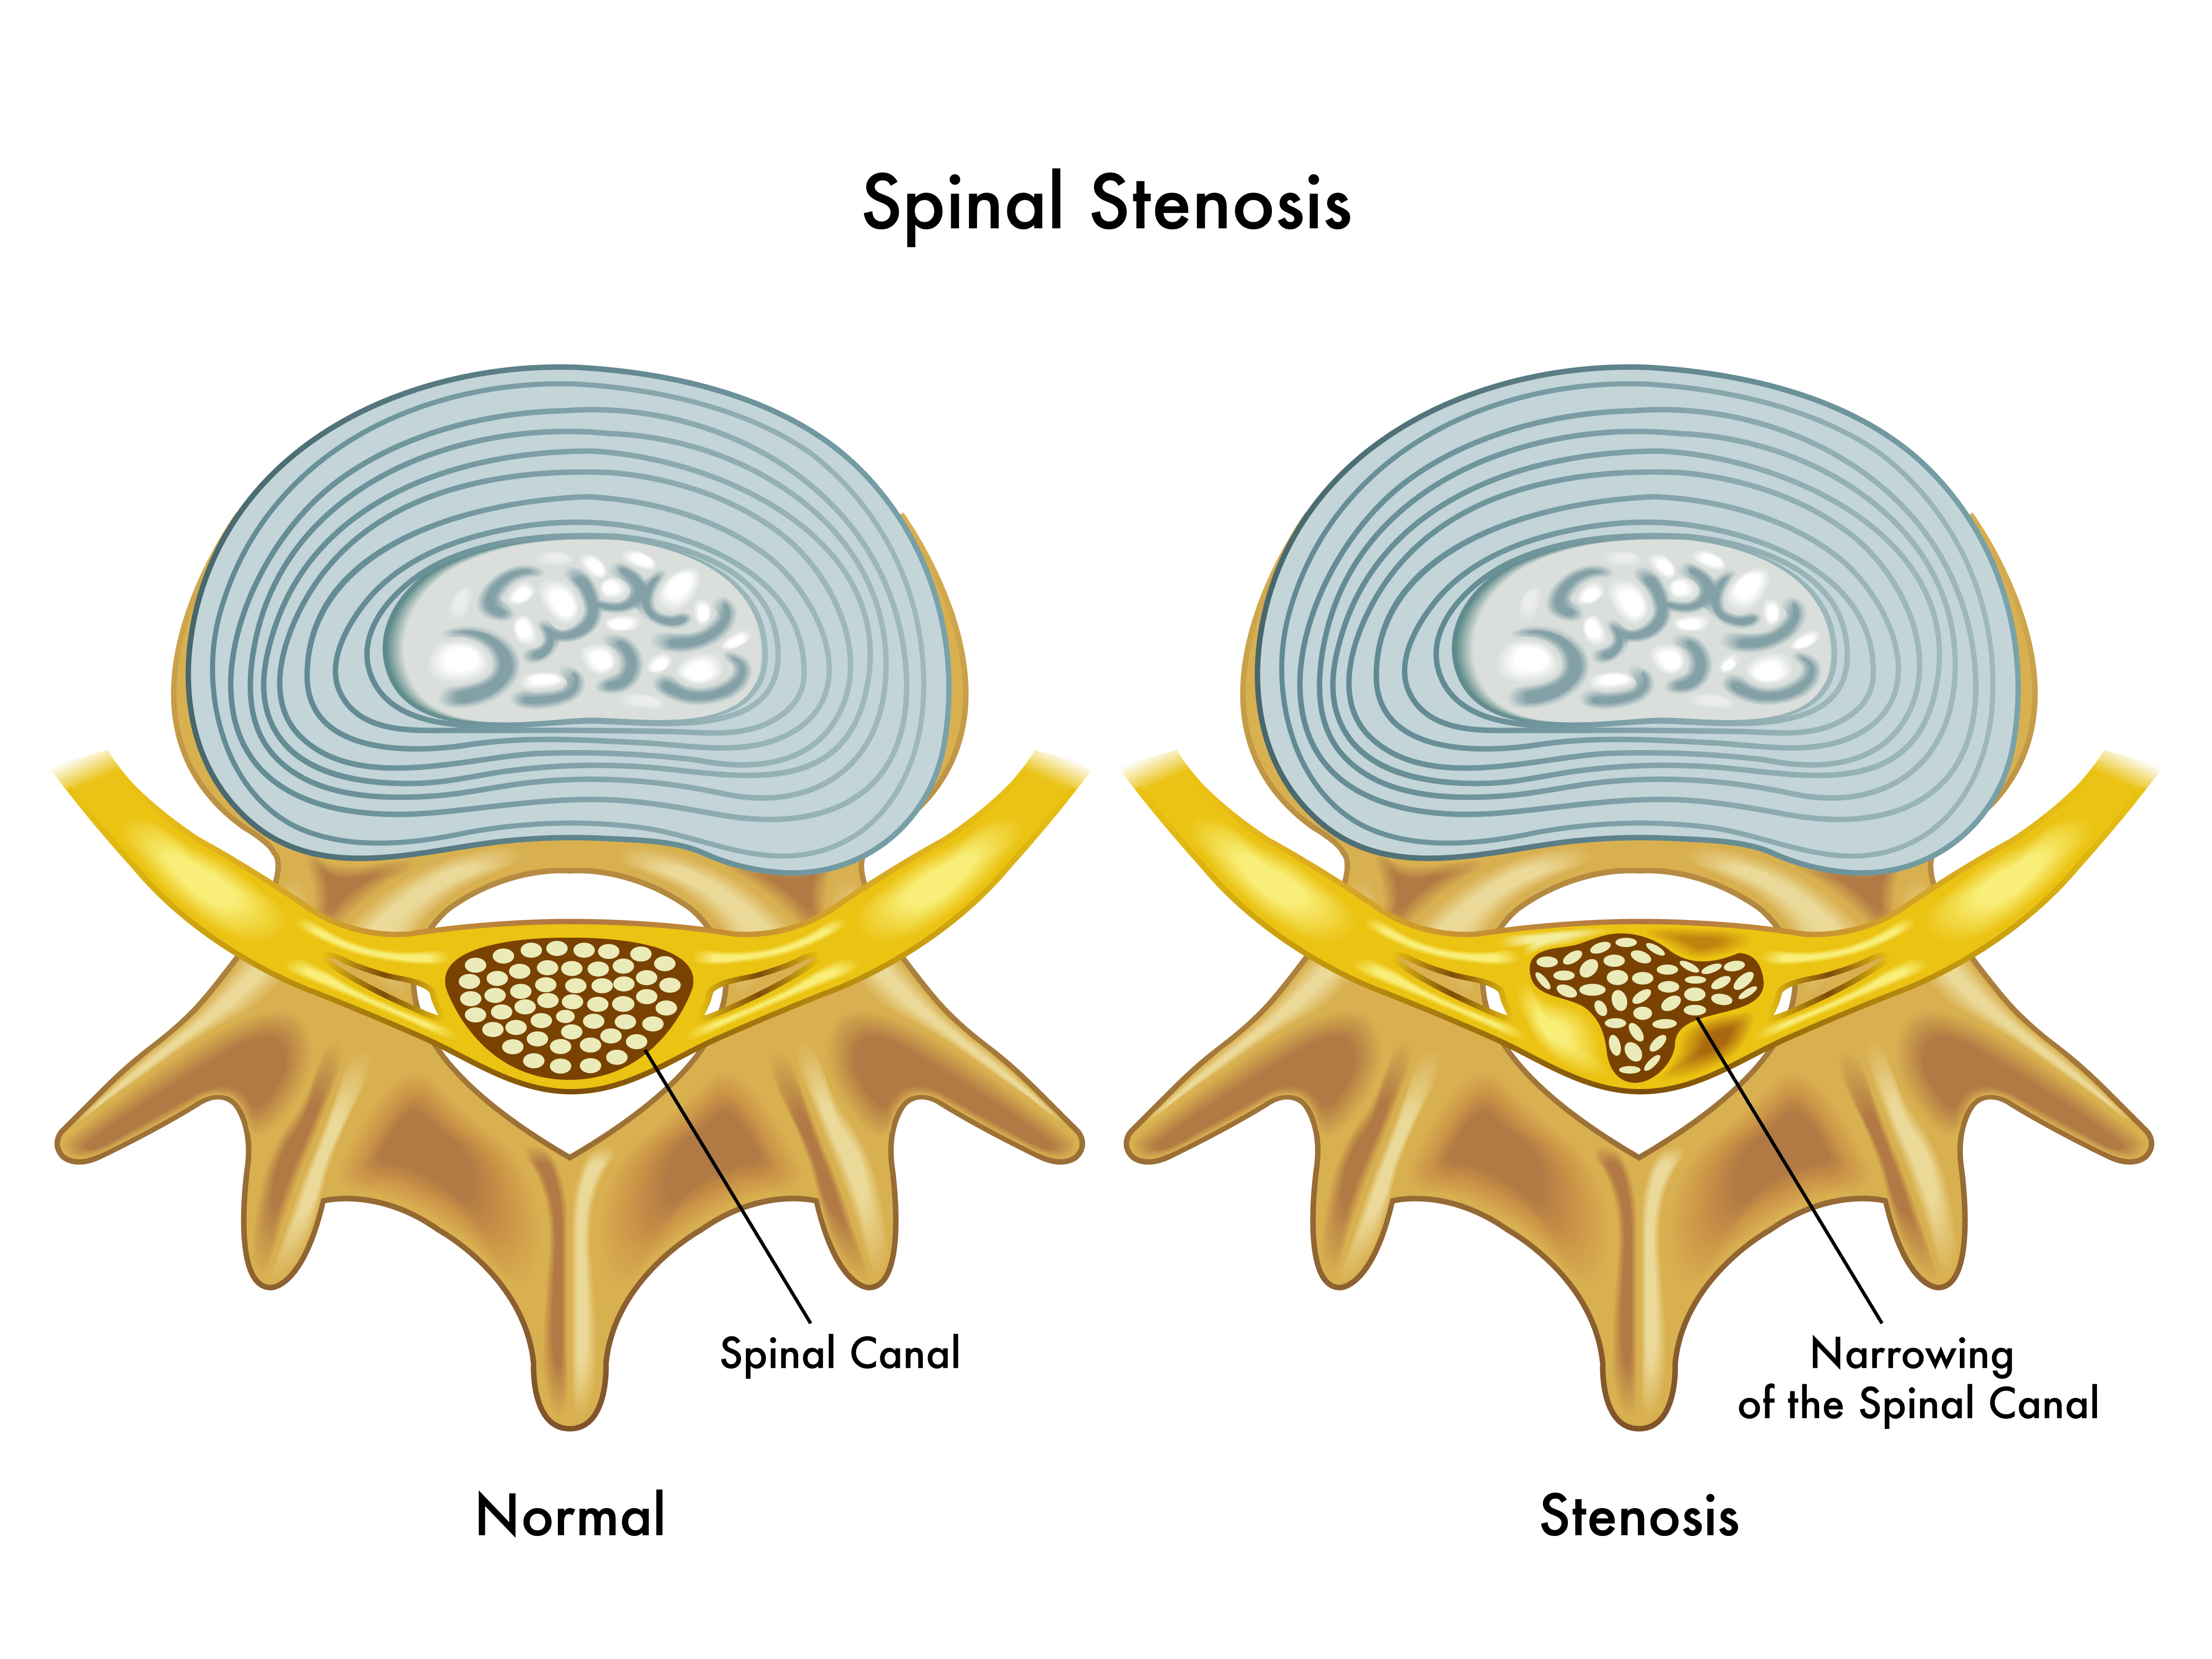

Spinal Stenosis Causes Symptoms Treatments

Spinal Stenosis Causes Symptoms Treatments